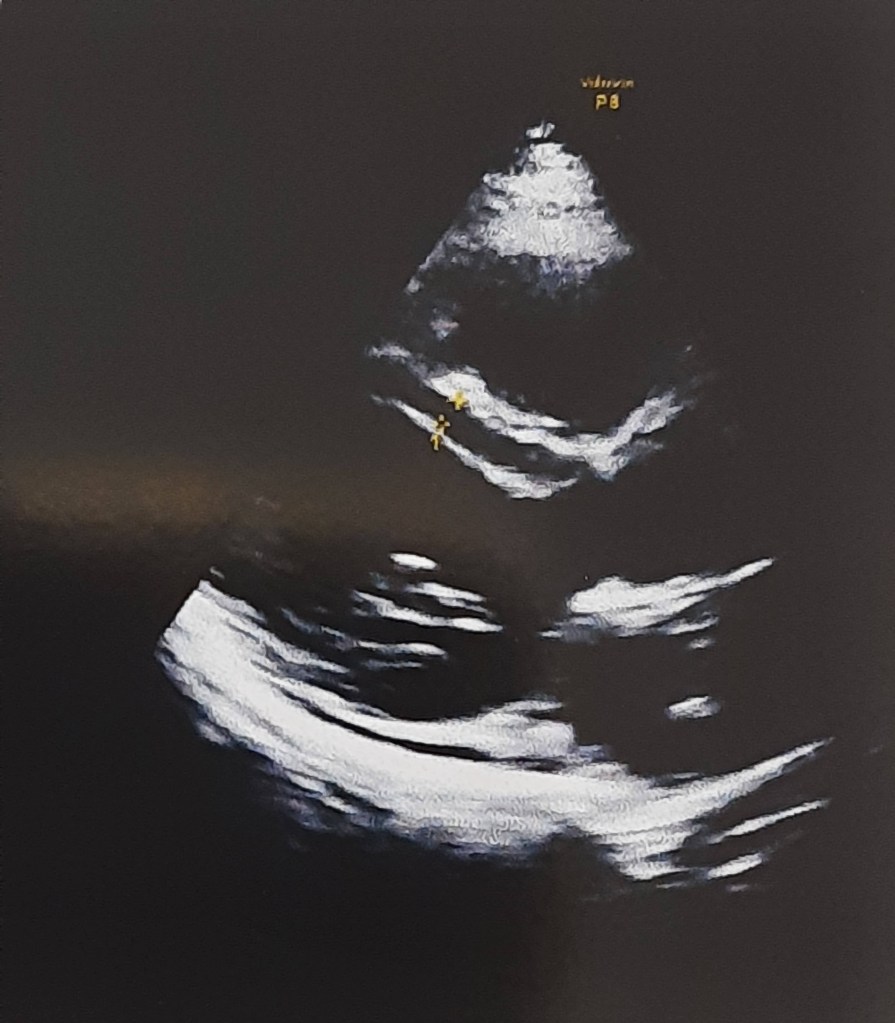

Assessing MR in echocardiogram: A well known tip

All of us know how tricky is, to assess and grade MR accurately. As discussed above it can as labile as systemic BP. Try to document the Heart rate and BP at the time of assesment.